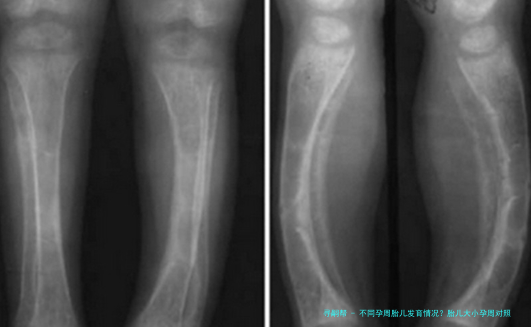

自然,每个宝宝的发育节奏不相同,有的快些许,某些慢些许,只要在正常范围内就不必太担心。医生也会通过B超来测量宝宝的双顶部直径、腹部周长、股骨长等指标,综合判断宝宝的成长情形。